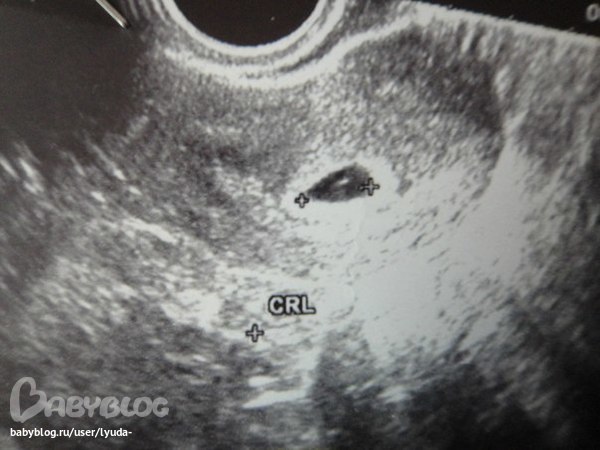

) Подскажите, на какой неделе (от месячных) можно уже увидеть бусинку?

Последние М были 30 ноября, а бусинку увидела уже 31 декабря, но сердце еще не билось, а потом в 12 недель видела ляльку уже во всей красе!